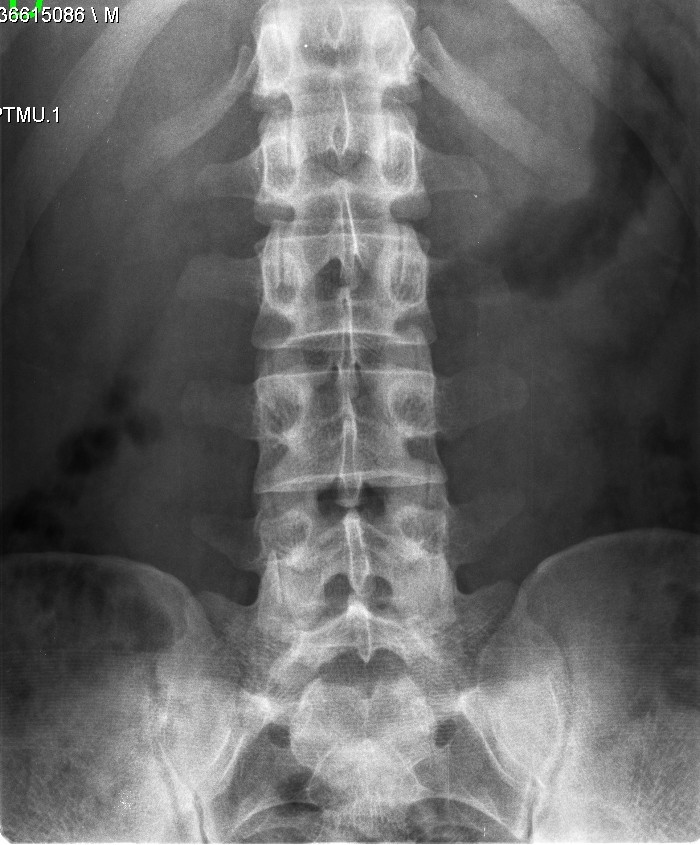

Vu00e9rtebra Transiciona Lumbosacra en una imagen de SCiardullo CC BY SA 40

Archivo.- Vértebra Transiciona Lumbosacra en una imagen de SCiardullo, CC BY-SA 4.0